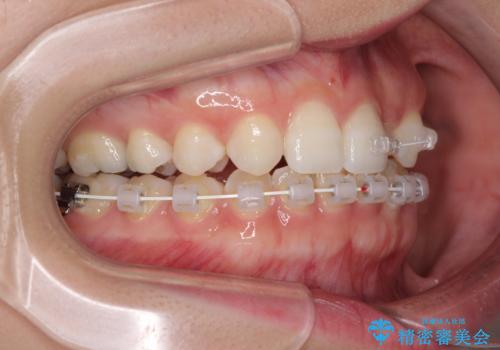

下顎は叢生が強かったため、奥歯までワイヤーを装着し、上顎は前歯の一部のみ気になっていたので、その部分にだけワイヤー装置を装着することとしました。